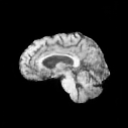

The results presented in Table 1 and 2 show our proposed method’s performance on unconditional 3D brain MR and chest CT image generation. Our proposed approach not only outperforms most comparing methods in FID and MS-SSIM metrics, it also has the lowest inference GPU memory footprint at a resolution of and was the only diffusion-based method that could be trained at a resolution of . Operating in the wavelet domain and profiting from the reduced spatial dimension also results in a relatively short inference time of / at the respective resolutions. Compared to the results presented in [23], we did not find that incorporating wavelet information into the network’s feature space (WavU-Net) increased the model’s performance. Qualitative results of our proposed method (WDM) are shown in Fig. 2 and 3. A qualitative comparison of samples produced by all evaluated methods can be found in the Supplementary Material.

We demonstrate our model’s performance on two publicly available datasets: BraTS 2023 Adult Glioma [1, 2, 15, 20] and LIDC-IDRI [14]. For training on the BraTS dataset, we use the T1-weighted brain MR-images, clip the upper and lower 0.1 percentile intensity values, zero pad the volumes to a size of and normalize them to a range of . For training on the LIDC-IDRI lung CT dataset, we initially clip all values below and the upper 0.1 percentile intensity values. We then resample the images to an isotropic voxel size of 1 , center crop them to a size of , and normalize to a range of . When training on images with a resolution of , we perform downsampling by applying average pooling.